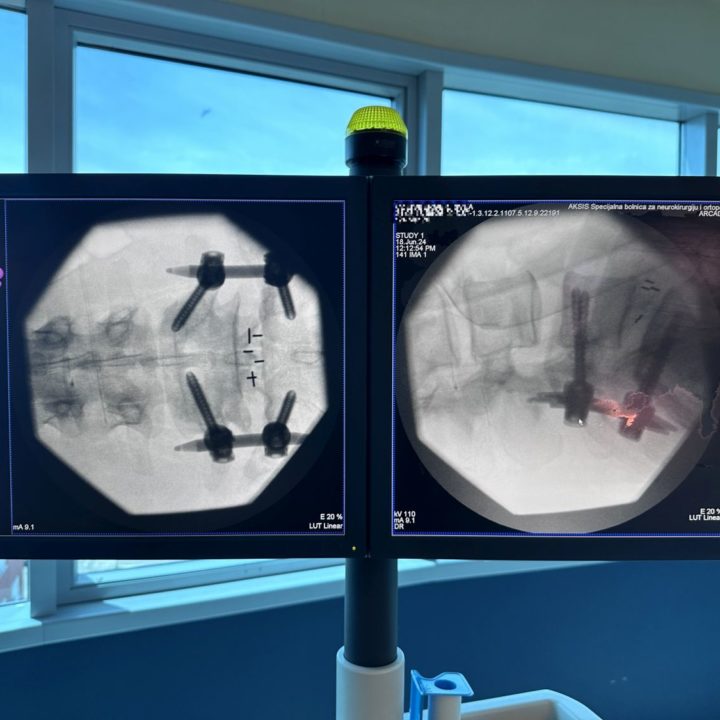

Ponosni smo na našu predanost i vrhunske rezultate u neurokirurgiji kralježnici. U zadnjih nekoliko dana naš izvanredni tim izveo je i dvije napredne i zahtjevne operacije kralježnice koje su pacijentima donijele olakšanje i poboljšanu kvalitetu života – METRx mikro-endoskopsku stražnju dekompresiju vratne kralježnice, te miniOpen TLIF spinalnu fuziju.

Naše iskustvo, znanje i tehničke mogućnosti omogućuju nam izvođenje najsloženijih zahvata s visokom stopom uspjeha. Zahvaljujući naprednoj tehnologiji i kontinuiranoj edukaciji naši neurokirurzi pružaju najbolju moguću skrb. U nastavku pogledajte slike koje prikazuju preciznost i inovativnost naših zahvata.